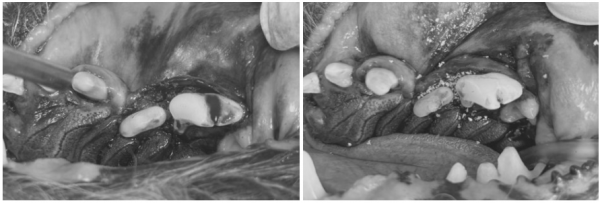

[진행한 치아 치료 과정 GBR/GTR(치조골 재생술)]

치아를 보존할 수 있는 좌측 어금니 부위는

다음과 같은 방식으로 보존 치료를 시행했습니다.

→ 해당 치아의 잇몸을 분리 후,

염증 조직을 제거하고 치은연하 스케일링을 진행한 뒤

→ 뼈 이식재를 해당 부위에 이식하고

차폐막을 삽입한 뒤 안전하게 봉합하였습니다.